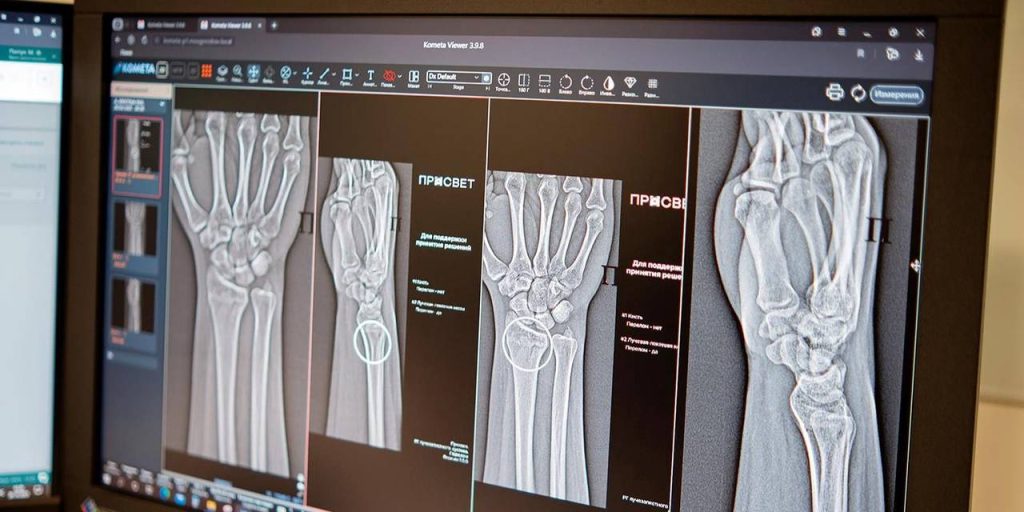

В столице начали функционировать две новейшие системы, базирующиеся на искусственном интеллекте и предназначенные для высокоточной диагностики переломов голеностопного и лучезапястного суставов.

Алгоритмы автоматически идентифицируют поврежденные участки и проводят необходимые измерения, даже при наличии нескольких переломов одновременно. Сегодня московские рентгенологи располагают более чем 60 ИИ-сервисами. Некоторые из них позволяют отличить норму от патологии, другие, например, измеряют границы и размеры аномалий. Эти сервисы применяются в 43 клинических направлениях, добавила вице-мэр Москвы.

По словам главного внештатного специалиста по лучевой и инструментальной диагностике Москвы Юрия Васильева, повреждения предплечья, кисти и голени встречаются довольно часто. Процедура выявления перелома включает осмотр врача-травматолога с последующим рентгенологическим исследованием. Специалисты применяют ИИ-алгоритм как ресурс, способный повысить точность и скорость анализа лучевого изображения, что играет решающую роль в установлении диагноза.